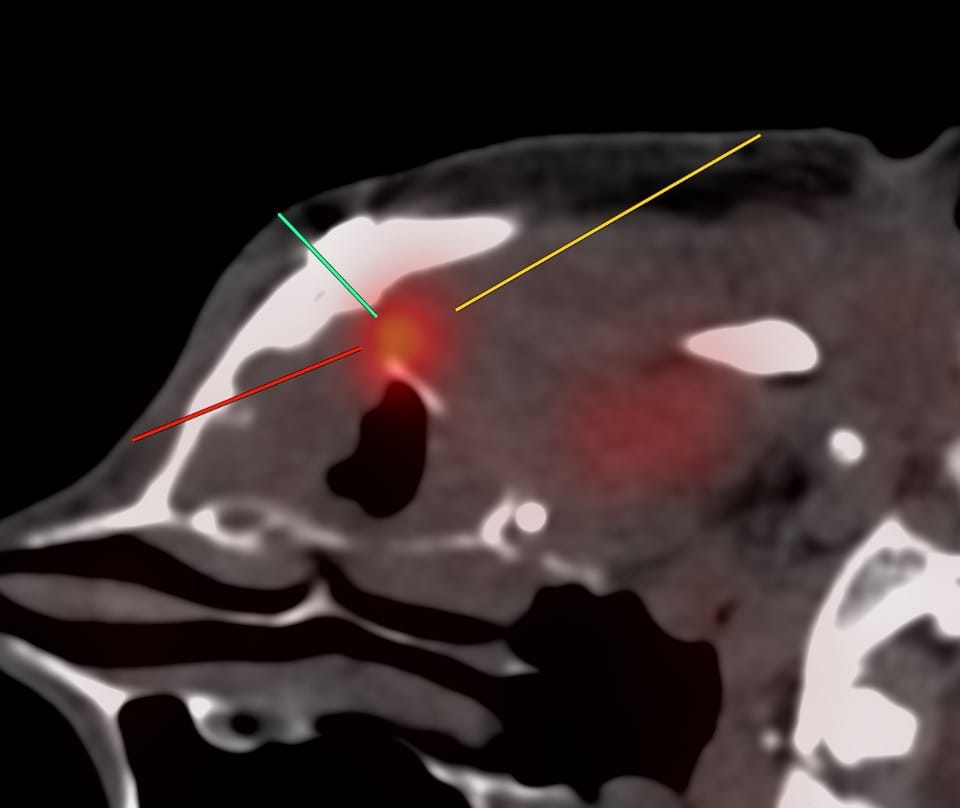

Position & Approach: Rt lateral decubitus, straight down, infrazygomatic

55-yrs old treated buccal ca with focal soft tissue and uptake on a follow-up PET in the left posterolateral maxillary sinus wall was referred for a CT guided biopsy.

Findings: Focal uptake posterolateral maxillary sinus wall

Lesion Biopsied: This lesion